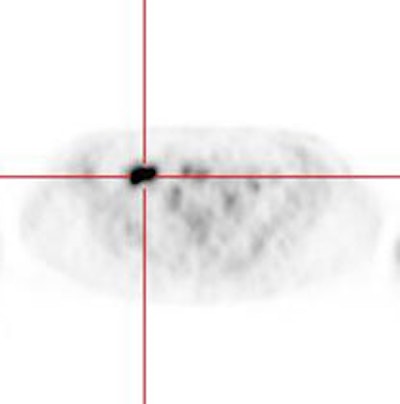

The stomach is usually faintly seen, but uptake can be intense - activity is seen only in the wall of the stomach (possibly related to smooth muscle activity) giving it a "ring-like" appearance [4,99,111]. However, if the stomach is not distended, uptake can appear focal- particularly in patients with prior partial gastric resection surgery [116]. Drinking a glass of water (some authors recommend 250 mL [228]) will produce gastric distention and benign uptake will generally become less conspicuous [116]. Focal gastric uptake should prompt further evaluation to exclude an underlying mass [156].

|

Gastric activity: Gastric activity can be very intense- even in patients without gastrointestinal disease. Note the "ring-like" appearance of normal gastric activity. |